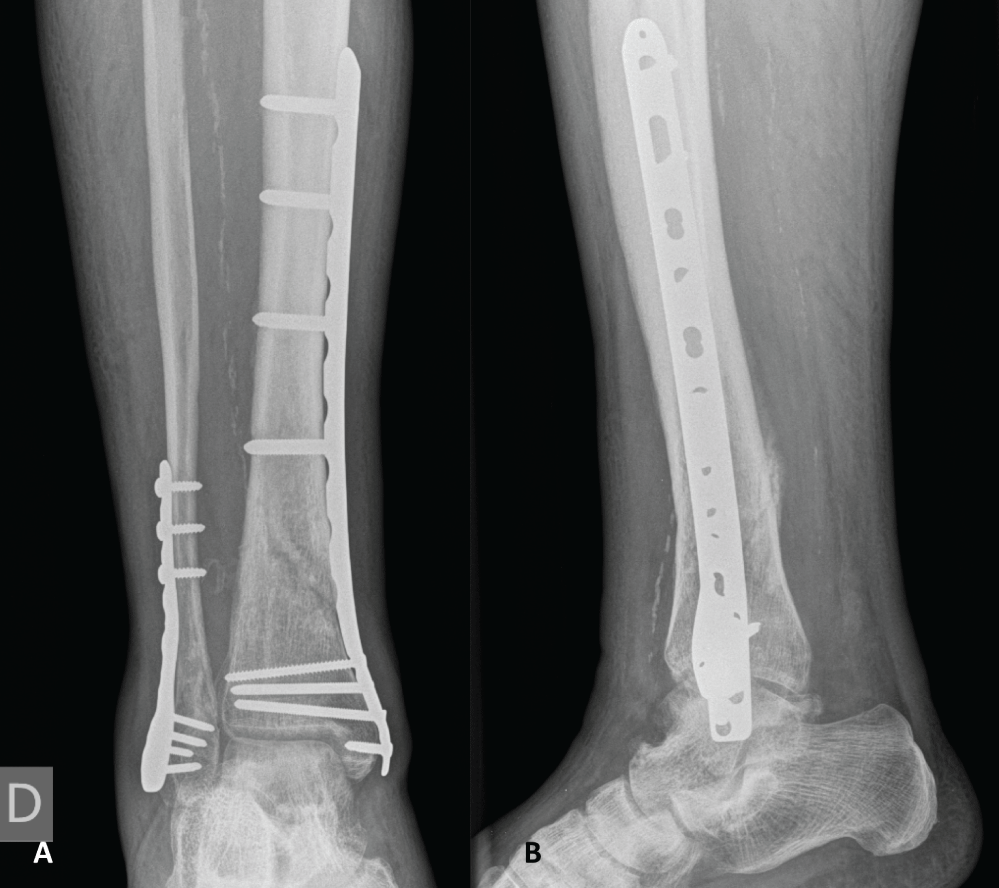

The second step consisted of the diaphyseal tibia fracture fixation using a standard MIPO technique. A 3 cm incision above the medial malleolus was made and a low profile anatomically pre-contoured 3.5/4.5 mm locking compression plate (LCP; Synthes®, Oberdorf, Switzerland) was subcutaneously inserted in a retrograde fashion. A 3 cm medial incision was made over the proximal end of the plate, 2 cm posteriorly to the anterior crest of the tibia. Reduction was obtained indirectly with manual traction of the limb under fluoroscopic guidance and confirmed by direct visualization through the anterolateral incision. After provisional fixation with 1.6 mm Kirschner wires, the plate was fixed proximally and distally with the appropriate locking screws. Due to swollen soft tissues over the lateral malleolus and poor skin quality, distal fibular fixation was postponed. The surgical wounds were closed and dressed in the customary manner. Upon operating room discharge, the foot was well perfused and pedal pulse was present on the operated side. Postoperative radiographs showed adequate fracture reduction (Figure 4).

Figure 4: Plain anteroposterior (A) and lateral (B) radiographic views following distal tibia fixation revealing adequate reduction. View Figure 4

Postoperative radiographs showed adequate fracture reduction. Wound healing occurred uneventfully. The patient was full weight bearing at 12 weeks and radiographs confirmed ongoing bone union at 16 weeks (Figure 5). At time of last follow-up, at 12 months, the patient was pain-free, active and ambulating, and radiographs showed complete bone union (Figure 6). Pedal pulse was present throughout follow-up and the patient had no complaints suggestive of vascular insufficiency of the affected limb. DPN function was preserved. Ankle range of motion reached a flexion-extension of 45-0-5° at last follow-up after intensive physiotherapy.

Figure 5: Plain anteroposterior (A) and lateral (B) radiographic views 16 weeks after definitive osteosynthesis demonstrating ongoing fracture consolidation. View Figure 5

Figure 6: Plain anteroposterior (A) and lateral (B) radiographic views 1 year after osteosynthesis showing complete fracture consolidation. View Figure 6